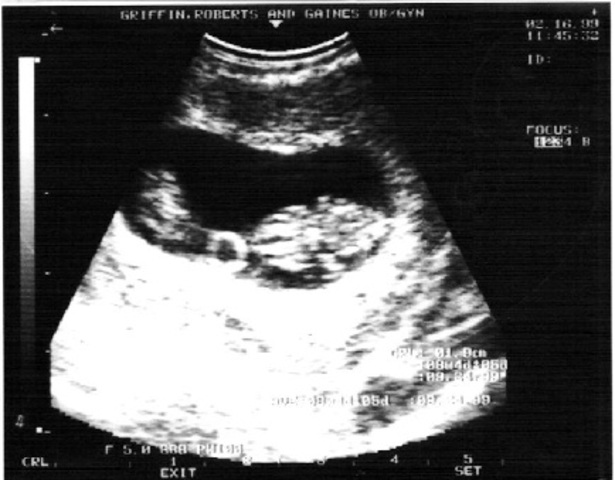

• Eyelids can open and weight can be up to 6.6 pounds.

Eyelids can open and weight can be up to 6.6 pounds.

A fetus between 6 and 9 months after conception can weigh 2.2 pounds. At that age, its eyelids can open. Stockarch, . eye2314. morgueFile. Web. 17 Feb. 2012.